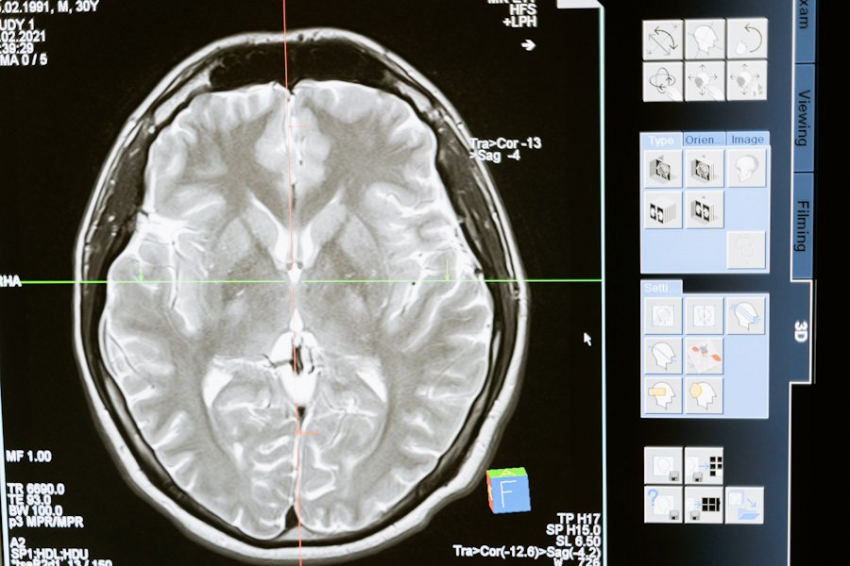

Канадские ученые из University of British Columbia впервые в истории зафиксировали электрическую активность мозга в момент смерти. Этот случай стал возможным благодаря несчастливой случайности: 87-летний пациент, страдавший эпилепсией, скончался от сердечного приступа прямо во время проведения электроэнцефалограммы (ЭЭГ).

Согласно изданию Live Science, исследователи отметили резкое увеличение интенсивности «гамма-осцилляций» — ритмичных электрических процессов, которые связаны с памятью, вниманием и узнаванием. Этот феномен породил гипотезу, что в последние мгновения жизни мозг пациента, возможно, воспроизводил прошлый опыт — как если бы вся жизнь «пронеслась перед глазами».